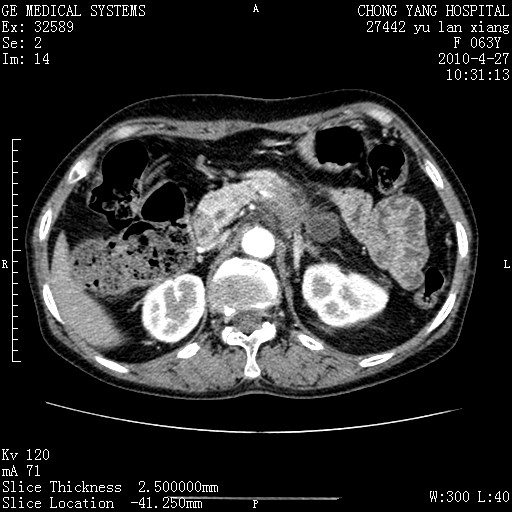

标题: CT26066:F63Y 上腹正中压痛半月,CA199:7400u/ml,MR示胰腺炎伴 [打印本页]

胰腺癌侵犯腹腔动脉干-分支、胃壁、左侧膈肌伴胰周及腹膜后淋巴结转移、胆囊切除术后。

胰腺癌侵犯腹腔动脉干-分支、胃壁、左侧膈肌伴胰周及腹膜后淋巴结转移、胆囊未显影。